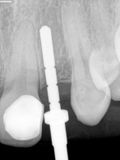

R2.jpg